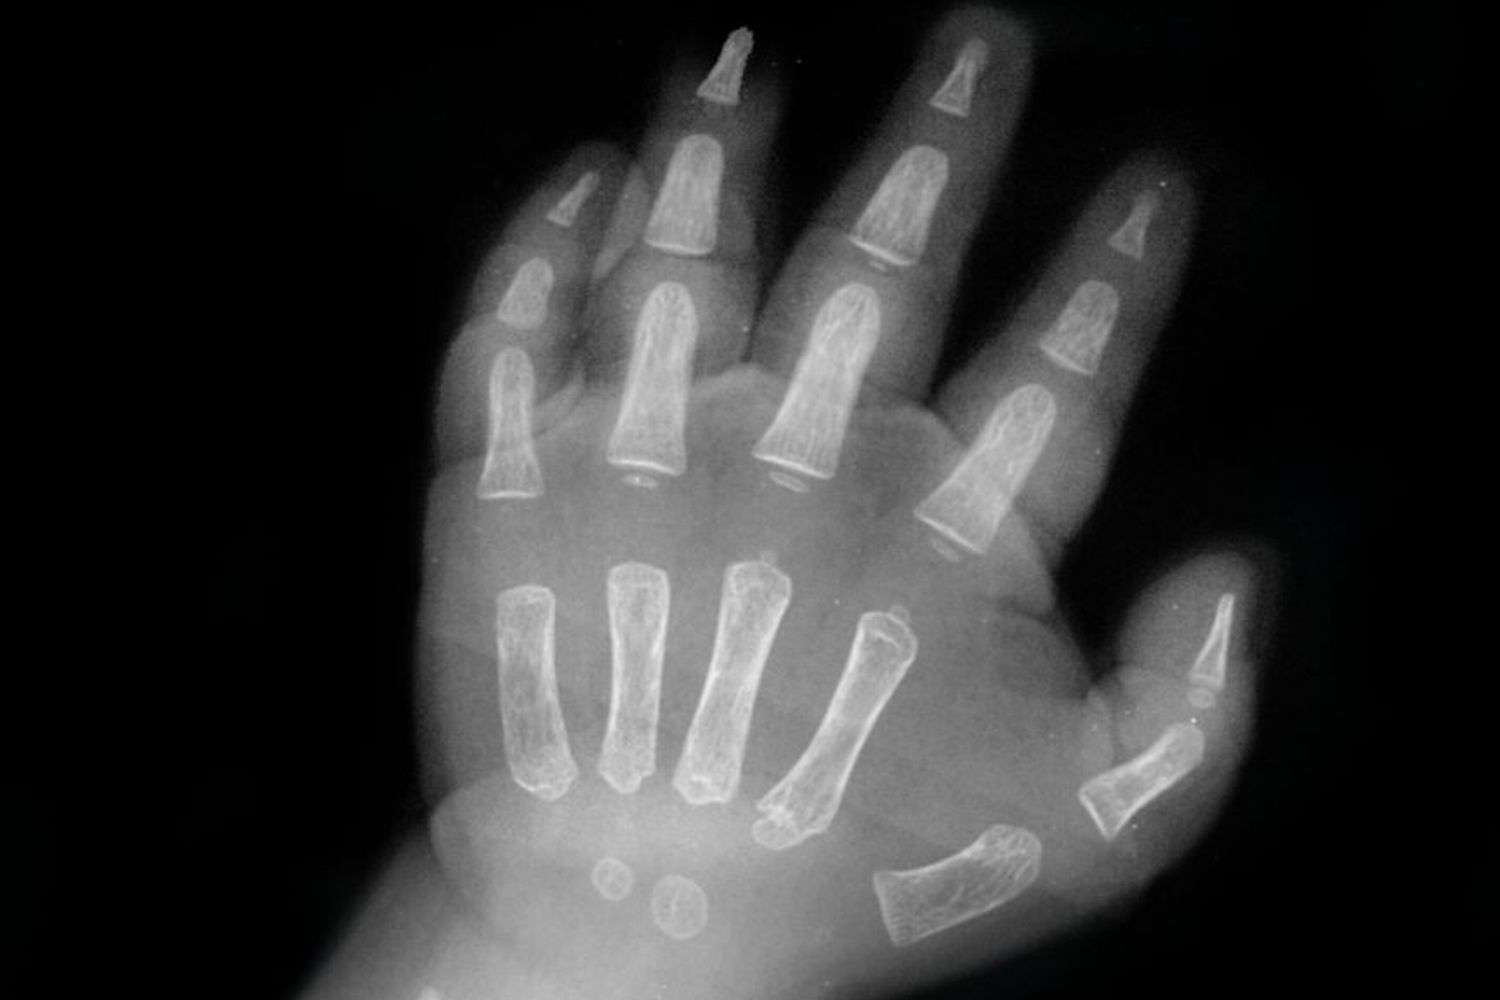

AGI - La bimba di 18 mesi rimasta con la mano nel tritacarne in un agriturismo di Ne, nell'entroterra di Genova, è arrivata in pronto soccorso con la mano che presentava alcune dita amputate. Il dottor Catena, direttore di Chirurgia della Mano del Gaslini, ha operato la bambina: il pollice non presentava lesioni ed è stato possibile ricostruire il mignolo, mentre le dita centrali della mano avevano subito traumi troppi gravi per essere salvate. Nelle prossime settimane sarà possibile valutare il grado di funzionalità residua della mano della bimba.